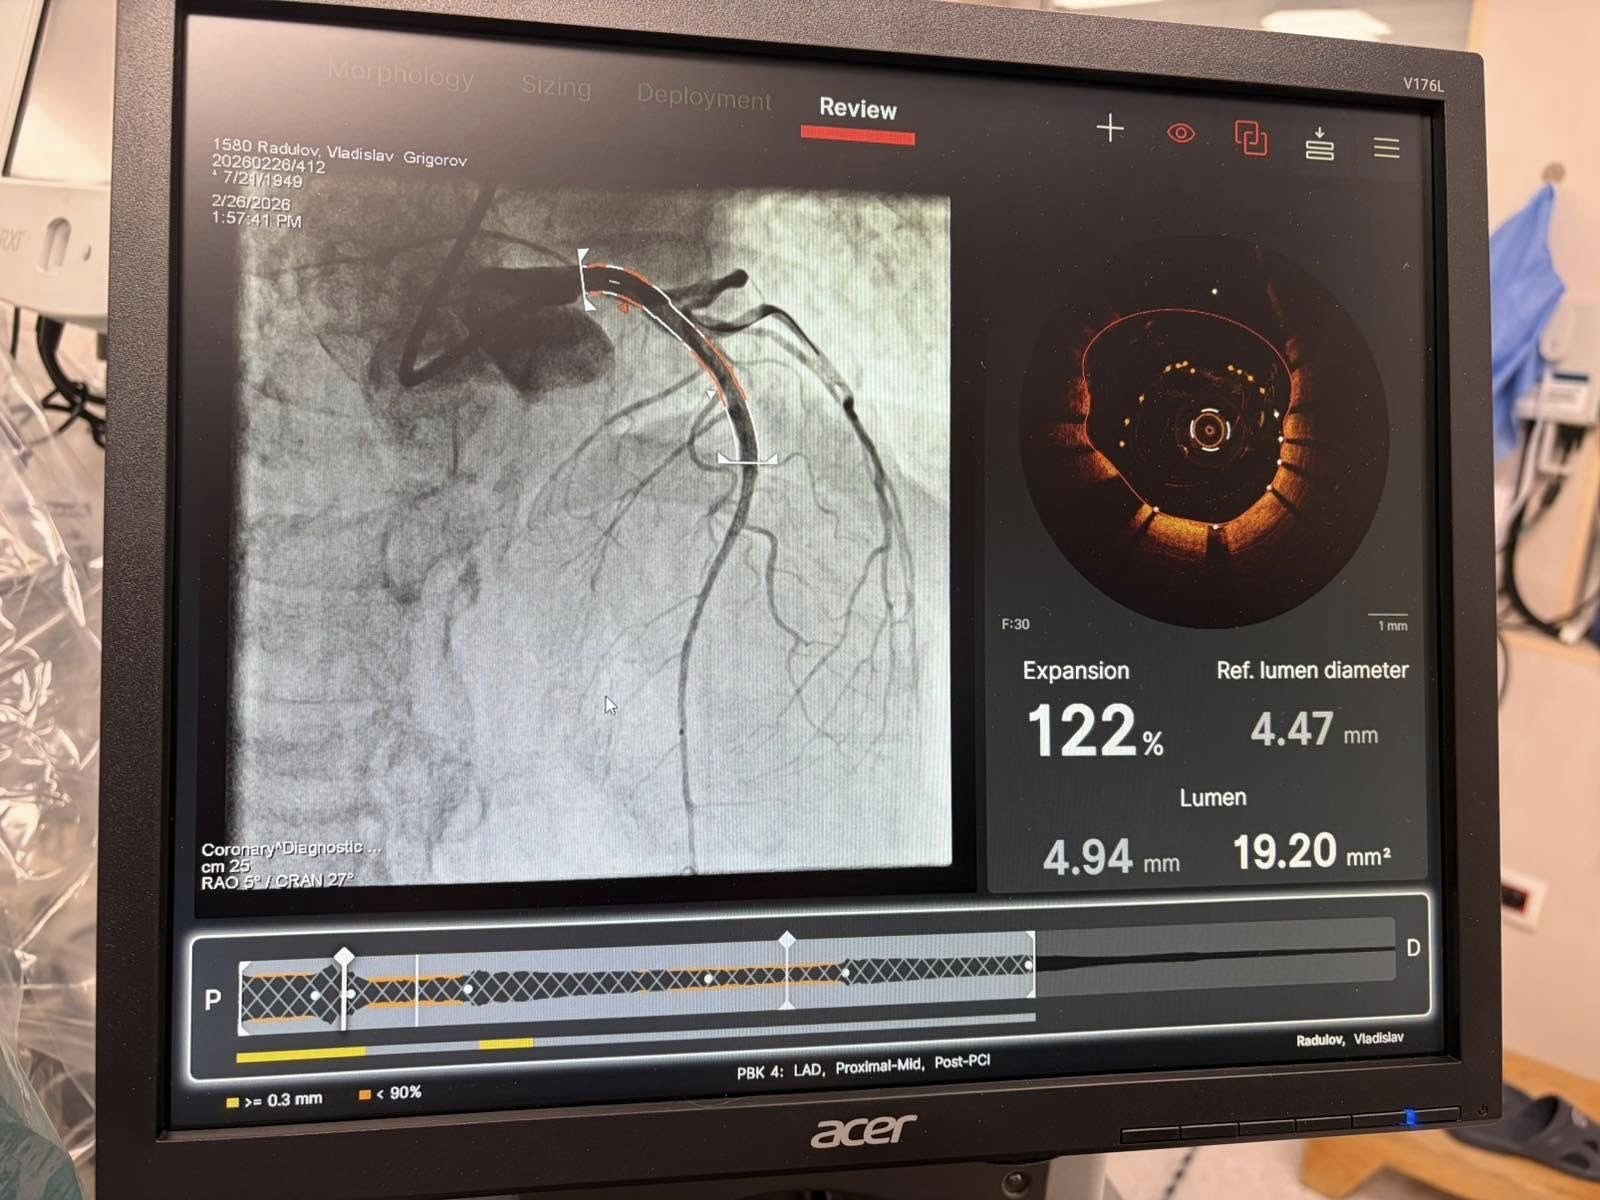

Под ръководството на д-р Александров, екипът на НКБ извърши комбинирана атеректомия под оптичен контрол – процедура, която звучи като сцена от научнофантастичен филм, но е реалност в софийската болница.

Всичко това се случва под безпощадния контрол на Оптичната кохерентна томография (OCT). Това е „златният стандарт“ в диагностиката, който чрез светлинни вълни предоставя на кардиолозите кристално чисто 3D изображение на вътрешността на артерията с микроскопична точност. Благодарение на OCT, лекарите виждат всяка подробност в реално време, гарантирайки перфектното поставяне на стента.